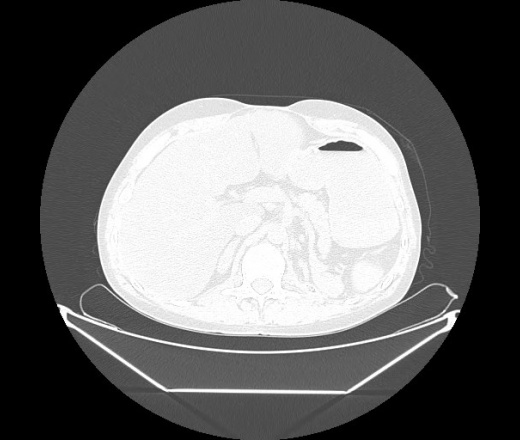

М. 1984 г.р.  Лихорадка 39, кашель , одышка.. и надоевший всем вопрос- "типично ли для ковид?" ( в настоящее время на него обязательно нужно дать ответ в своем протоколе)

На мой взгляд нетипично для ковид: много центрально-расположенных поражений, лобарное поражение нижней доли слева. 50/50

Не типичая картина для ковид.

КТ-признаки двусторонней бактериальной пневмонии.

Все верно, здесь абсолютно нетипичная картина, несмотря на матовое стекло с ретикулярными изменениями, но почему-то  посчитали иначе. Кстати,  "малыша" не заметили)?

Добавил 6 день

Что за малыш? Будущий абсцесс? Не заметил. Только о туберкулёзе подумал

+ 1?  Зона очень похожа была на формирующийся абсцесс, даже по рентгенпризнакам. Еще хотела спросить, но постеснялась. А на контроле видно

да, это я о абсцессе.